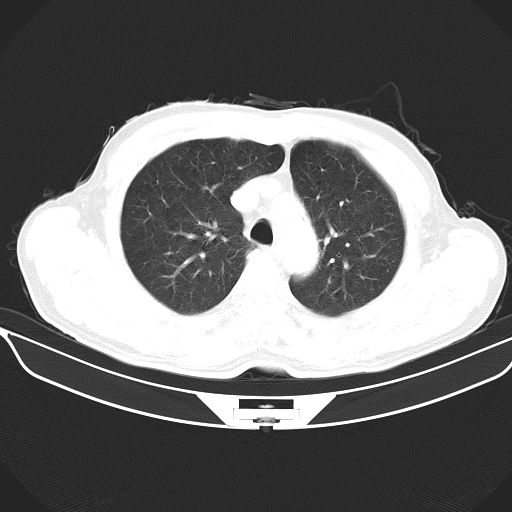

以下是引用心路寻觅在2010-3-1 10:23:00的发言:[br]1、考虑左肺上叶周围型肺癌[br]2、右上肺陈旧性病灶。[br][br][本贴已被 心路寻觅 于 2010-3-1 10:40:18 修改过]

以下是引用shuiyuan在2010-3-1 10:45:00的发言:[br]考虑左肺上叶中心型肺癌伴阻塞型炎症,邻近胸膜受侵。